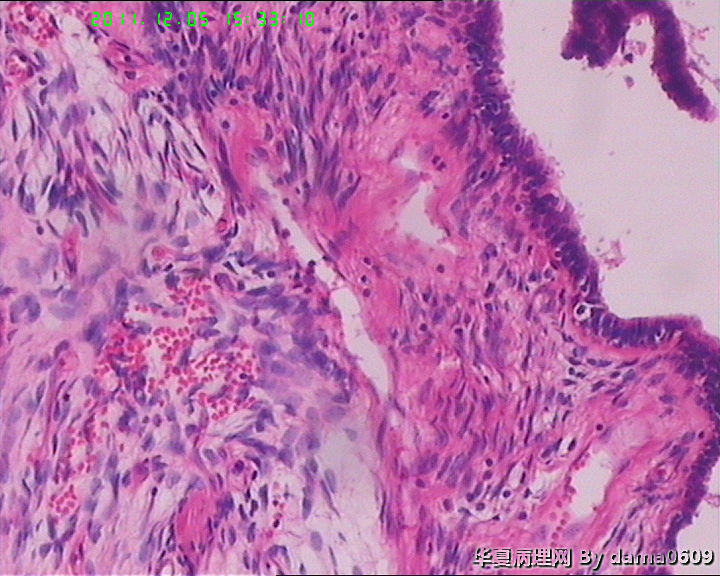

肿物一:镜下见乳腺小叶结构紊乱,小叶内、小叶间间质增生,构成肿瘤主质。增生间质呈梭形细胞样,细胞稀疏、异性不明显,其间见大量胶原纤维,小血管增生,局灶有红细胞渗出。见到一处导管大汗腺化生。

肿物二:镜下呈结节状,结节以导管或小叶为中心,围以增生的间质成分,梭形细胞构成,稀疏,增生的血管呈“鹿角状”。大结节内见局灶间质有出血或红细胞外渗,局灶导管内间质增生呈乳头/分叶状,上皮下无密集增生的间质细胞。结节大小不等,以窄带样纤维细胞束彼此分隔,互不融合,纤维细胞束细胞密集,内有增生的小血管。

老师:这一例学生考虑:1、乳腺纤维腺瘤。问题:患者年龄较大,肿物梭形细胞的间质成分增生显著,上皮成分增生与之不协调,内有大量胶原成分及增生的小血管,还有出血等,结构复杂,尤其肿物二的结节状结构何来?

2、叶状肿瘤(良性)。问题:叶状结构不明显,上皮下不见显著增生的梭形细胞,肿物二的结构也似乎不对。